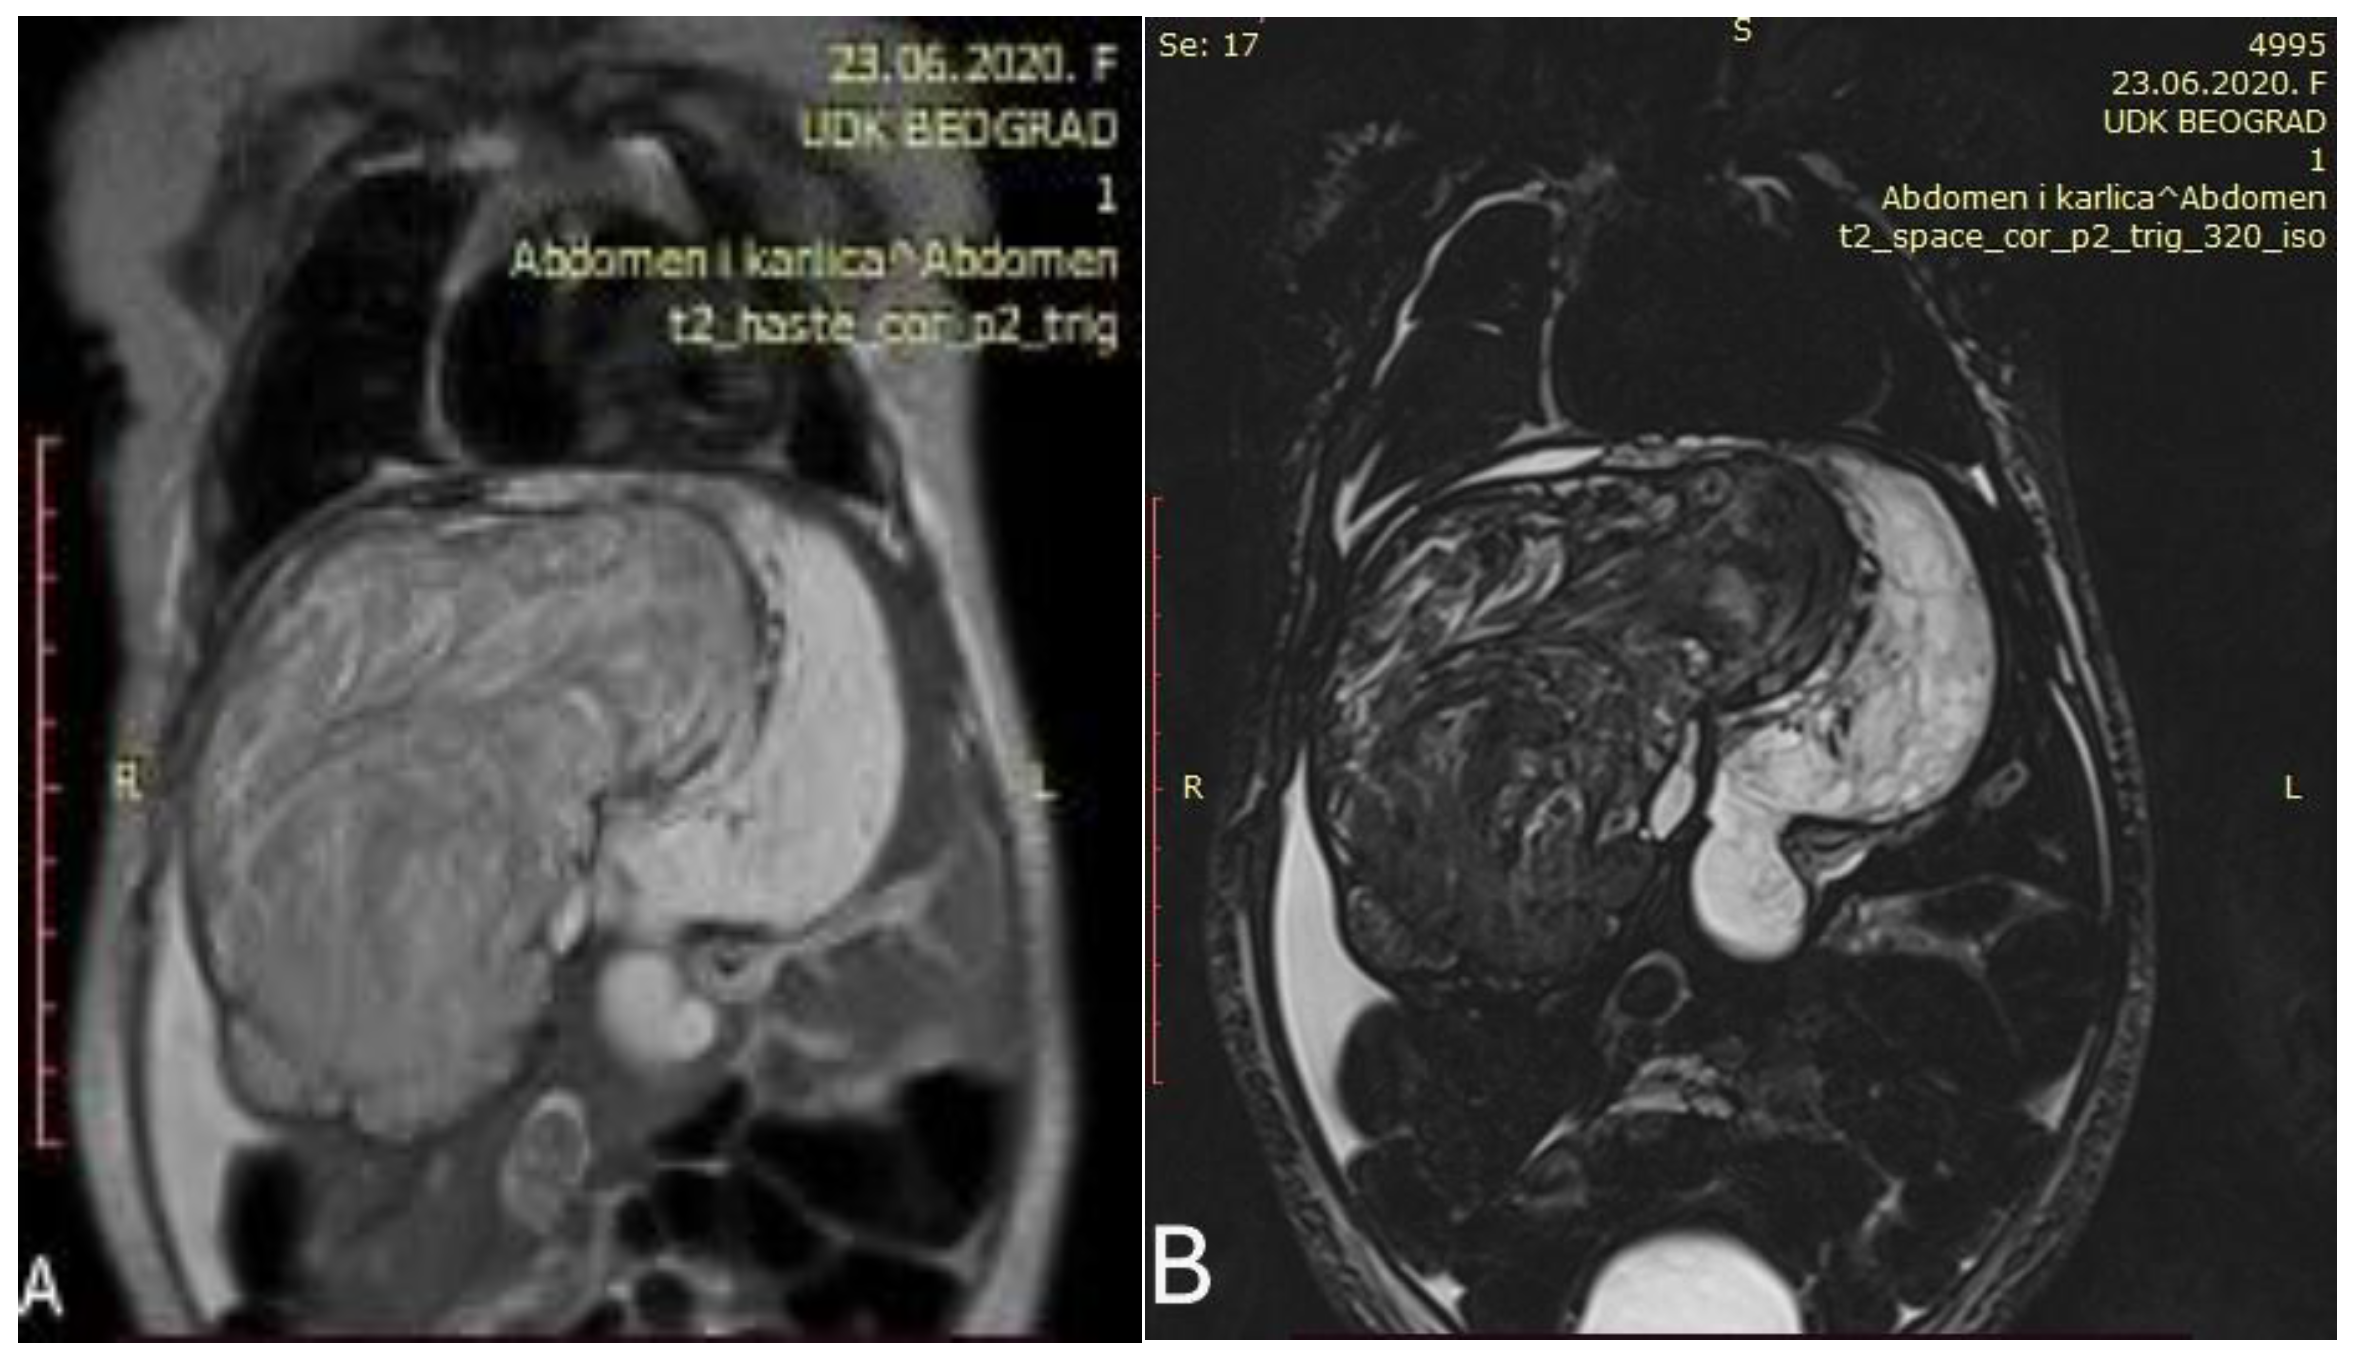

Abdominal MRI revealed a large heterogeneous liver mass that infiltrates most of the right liver (except Couinaud segment VI and VII) and almost the entire left lobe, measuring 120 mm × 85 mm × 78 mm with signs of parenchymal bleeding and necrosis (Figure 2).

Initial abdominal MRI showed a voluminous heterogeneous tumor occupying the right liver ((A,B) Different coronal slices of the same MRI).

Control abdominal MRI showed a significant decrease in the initial tumor mass (62 mm × 47 mm × 45 mm) with mostly cystic and necrotic morphology (Figure 3). The right hepatic vein was intact, the intermediary hepatic vein went straight through the tumor, and the left hepatic vein encircled the tumor next to its border. Both portal vein branches were intact as well as the inferior vena cava and hepatic arteries.

Control abdominal MRI after six cycles of chemotherapy showing a significant decrease in the tumor mass ((A) showing the coronal plane view of the MRI; (B) showing the axial plane view of the MRI).